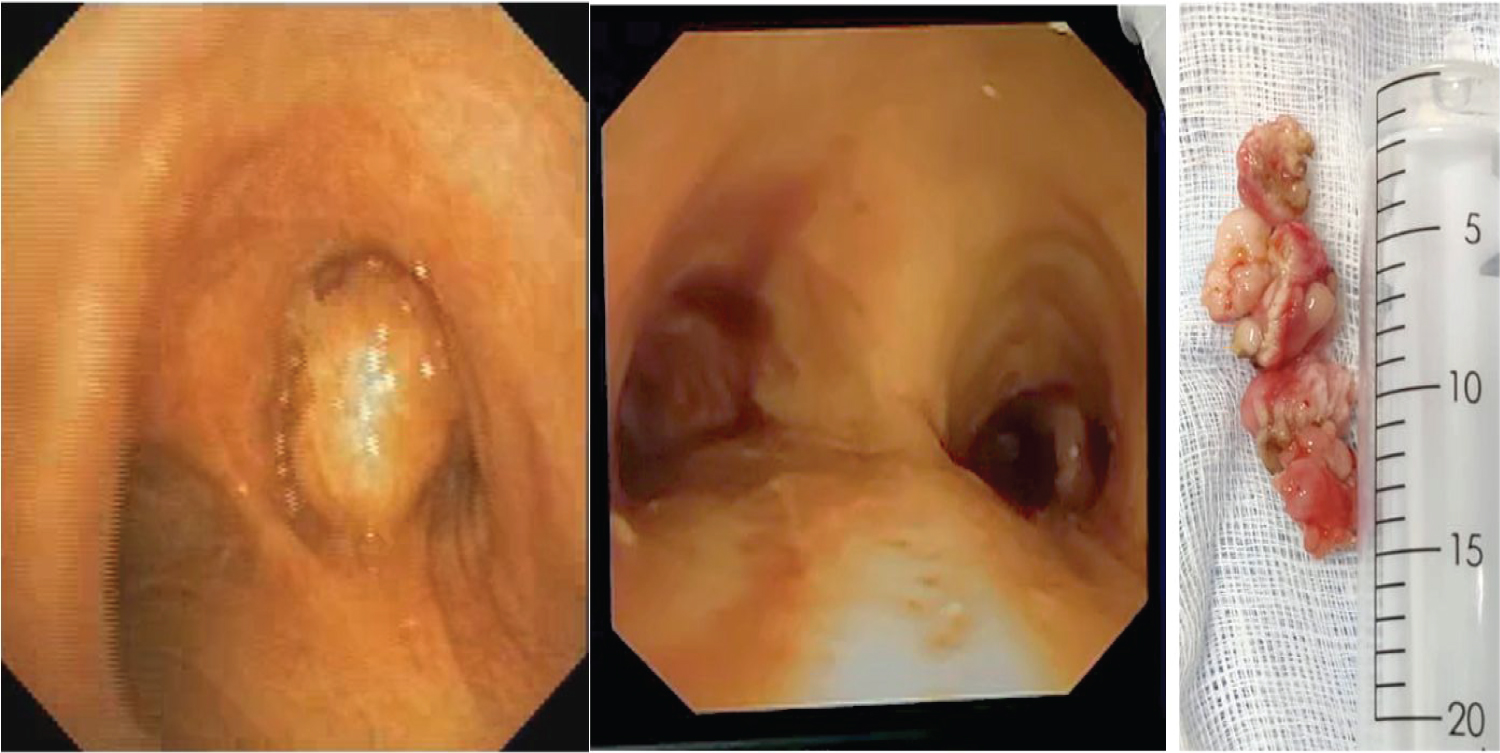

A 66-year-old male, diabetic and hypertensive presenting with fever and cough for a week was diagnosed to have right endobronchial growth (Figure 1) and post obstructive pneumonia in right lower lobe, confirmed with Chest X-ray (Figure 2), Computed Tomography (CT) Thorax and flexible bronchoscopy (Biopsy - squamous metaplasia). Pre-operative optimization included a course of antibiotics and bronchodilator therapy. Consent included explanation of risks of airway bleeding, trauma, perioperative airway oedema and remote chances of postoperative ventilation. Sedation the day before surgery was avoided. Standard monitoring was done. Well-functioning suction apparatus, Double lumen tube (DLT) and bronchial blocker were kept standby for lung isolation in case of massive airway bleeding. Maximum allowable neck extension was checked prior to induction with shoulder roll and head ring. Patient was preoxygenated with 100% Fraction of Inspired Oxygen FiO 2 , premedicated with glycopyrrolate 10 µg/kg, ondansetron 0.15 mg/kg, fentanyl 2 µg/kg and induced with propofol 2 mg/kg and paralyzed with atracurium 0.5 mg/kg. 11 mm rigid bronchoscope was passed after positioning with neck extension by pulmonologist. Ventilation was done via side port with intermittent apnoeic periods. Arterial line was secured and transduced. Anaesthesia was maintained with propofol infusion 10-15 mg/kg/hr throughout the case, depth of anaesthesia monitored by Bispectral Index (BIS) adjusted to 40-60. Analgesia was provided with repeated doses of fentanyl 0.5 µg/kg at half hourly intervals and IV paracetamol 1g. FiO 2 was kept at 0.5 and reduced to 0.3 at the times of cautery use to prevent airway burns. Higher flows of 5 to 6 litres/minute were used throughout the case. Atracurium boluses of 10 mg was given every 30 minutes. Blunting of sympathetic responses was done with esmolol infusion, bolus of 500 µg/kg over 10 minutes followed by infusion of 50-100 µg/kg/min. Steroids in the form of intravenous hydrocortisone 100 mg and dexamethasone 8 mg was given to prevent airway oedema. Endobronchial mass was detached using electrocautery and extraction was done piecemeal using cryoprobe as it was difficult to remove en masse. Minimal bleeding was noted, managed by suctioning. Final check scopy showed patency of all bronchi. Thorough suctioning and xylocard 1 mg/kg sprayed into the airway at the end of procedure. After removal of bronchoscope intubation with size 8.0 mm endotracheal tube was done and ventilated for about 15 minutes. Arterial Blood Gas (ABG) done following the procedure was normal. Patient was extubated uneventfully and was monitored in Intensive Care Unit (ICU) for 24 hours. We did not encounter any significant postoperative complications.

Figure 1: Bronchoscopic view of carina before and after removal of right endobronchial tumor and picture of gross specimen (case 1). View Figure 1

A 35-year-old male, presented with respiratory symptoms was diagnosed to have left main bronchus growth, confirmed with CT Thorax and bronchoscopy (Figure 3). Antibiotics and bronchodilators were given. Written informed consent was taken. Patient was shifted to Operation Theatre (OT); standard monitoring including invasive arterial monitoring was done. The extent to which cervical extension was comfortable to the patient was checked preoperatively. After induction of anesthesia with propofol and atracurium, 11 mm rigid bronchoscope was passed, ventilation via side port was done. Anaesthesia was maintained with propofol infusion 10-15 mg/kg /hr with BIS monitoring. Intraoperative analgesia was with fentanyl and paracetamol. FiO 2 was reduced to 0.3 at the times of cautery. Higher flows were used. Atracurium boluses were given. Sympathetic responses were blunted with dexmedetomidine infusion (bolus 1 µg/kg followed by infusion of 0.3 µg/kg/min) and esmolol infusion of 50-100 µg/kg/min was used as rescue. Steroids were gives. As the mass was in the left bronchus (larger angulation) the access was difficult to remove by electrocautery. Only part of Endobronchial mass could be detached from the wall and piecemeal extraction with cryoprobe was done. Significant bleeding was noted, managed by suctioning and cautery. No desaturation was observed. DLT and bronchial blocker was kept standby for lung isolation in case of massive airway bleeding. Final check scopy showed patency of all bronchi. Post procedure intubation was done and patient was extubated uneventfully and monitored in ICU for 24 hours. We did not encounter any significant postoperative complications.

Figure 3: Bronchoscopic view of left endobronchial tumor (case 2). View Figure 3